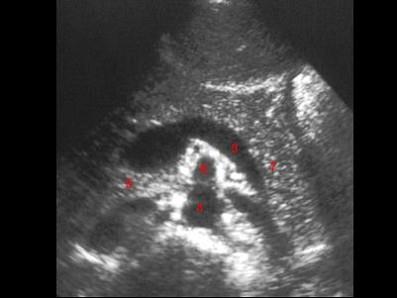

图示4所指部位?(?)A.脾静脉B.腹主动脉C.肠系膜上动脉D.胰头E.下腔静脉

问题 图示4所指部位?(?)

选项 A.脾静脉 B.腹主动脉 C.肠系膜上动脉 D.胰头 E.下腔静脉

答案 B